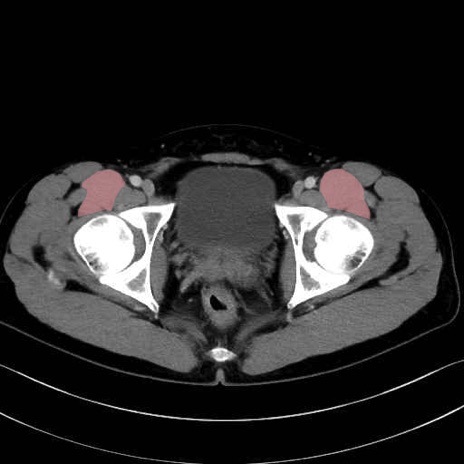

腸骨筋 (Iliacus)

大殿筋 (Gluteus maximus)

中殿筋 (Gluteus medius)